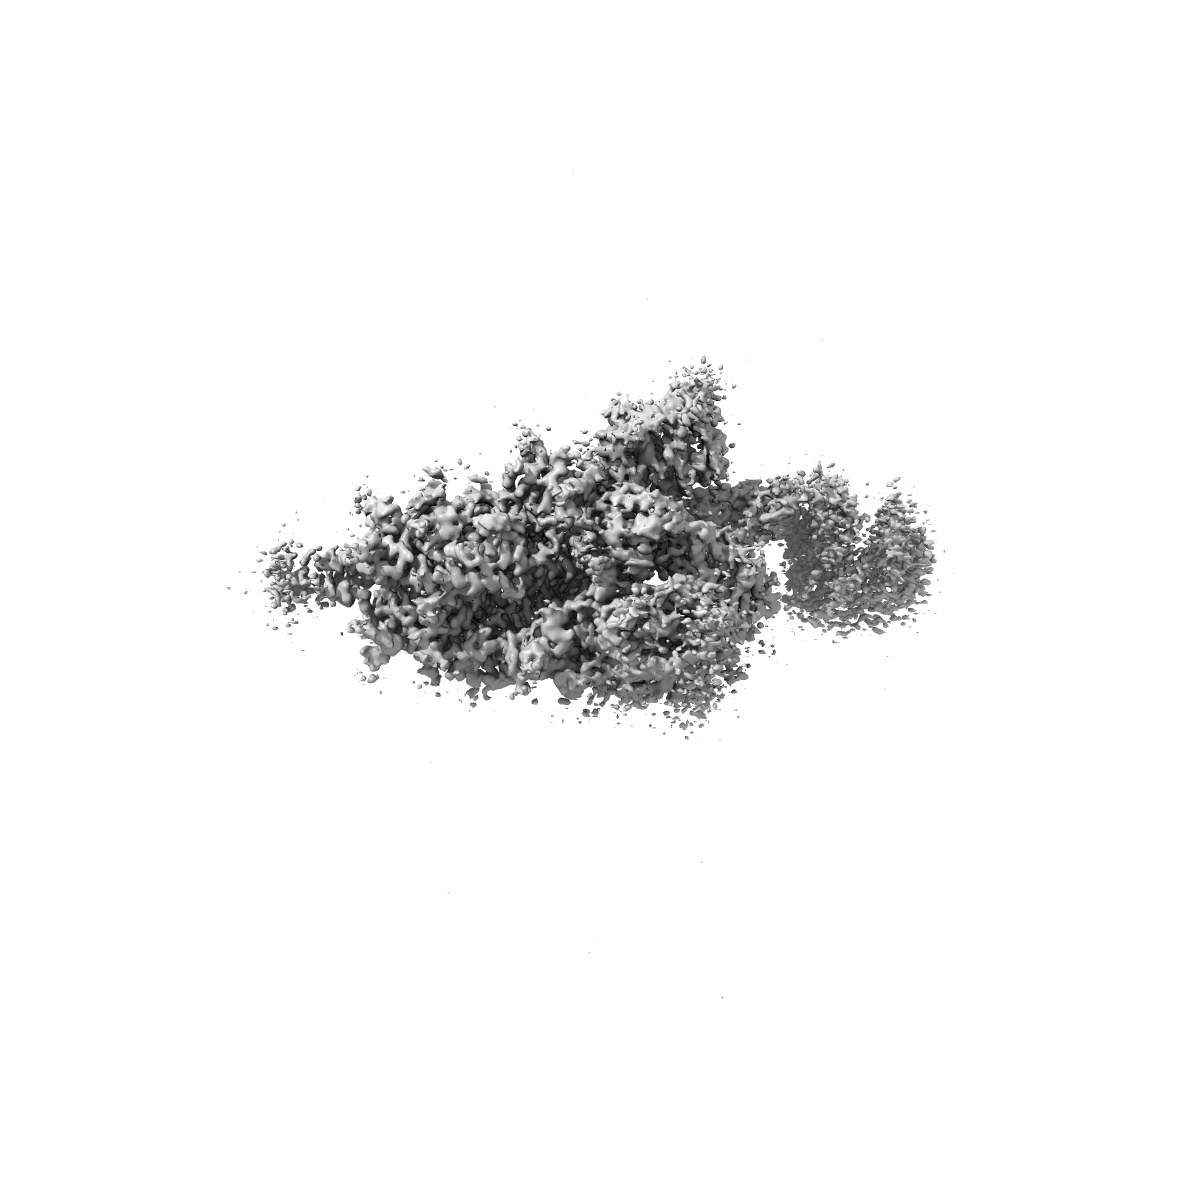

Cryo-EM structure of SARS-CoV-2 XBB.1.5 spike protein in complex with mouse ACE2 (conformation 1)

Sample: SARS-CoV-2 XBB.1.5 spike protein trimer bound to mouse ACE2